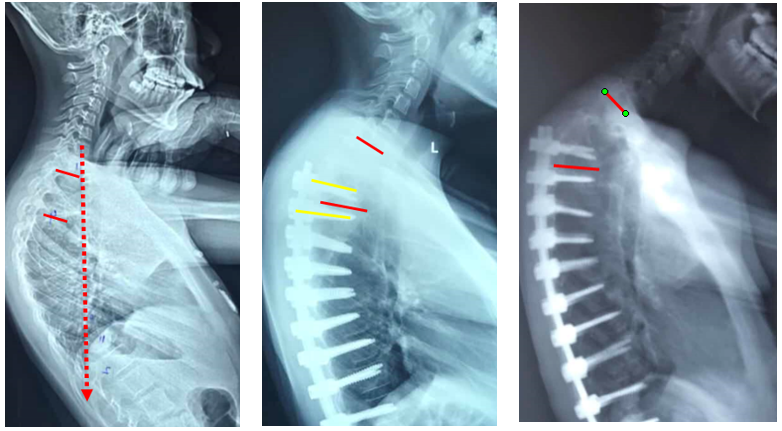

(2)上固定椎在交界区或存在交界性后凸

图6 长节段融合固定上固定椎(UIV)选择在胸10-12胸腰椎交界区是PJK的风险因素之一

1) 矢状面失平衡(High SVA)过度矫正

术前-术后SVA矫正过大(大于5cm)的患者,PJK发生的风险增高

矫形术后矢状面失平衡可增加固定融合近端和远端交界区的应力,增加PJK风险

图16 矢状面失平衡过度矫正

2)腰椎前凸(LL)过度矫正

图17 据文献报道,腰椎前凸(LL)过度矫正和SVA基线位置不当,均为增加PJK发生的风险因素

图18 固定近端交界性后凸角>5°

A:术前固定近端交界性后凸角>5°;B:上固定椎未跨过此区域;C:术后随访出现PJK

Ø 颈7铅垂线距离UIV太远

图19 颈7铅垂线距离UIV太远